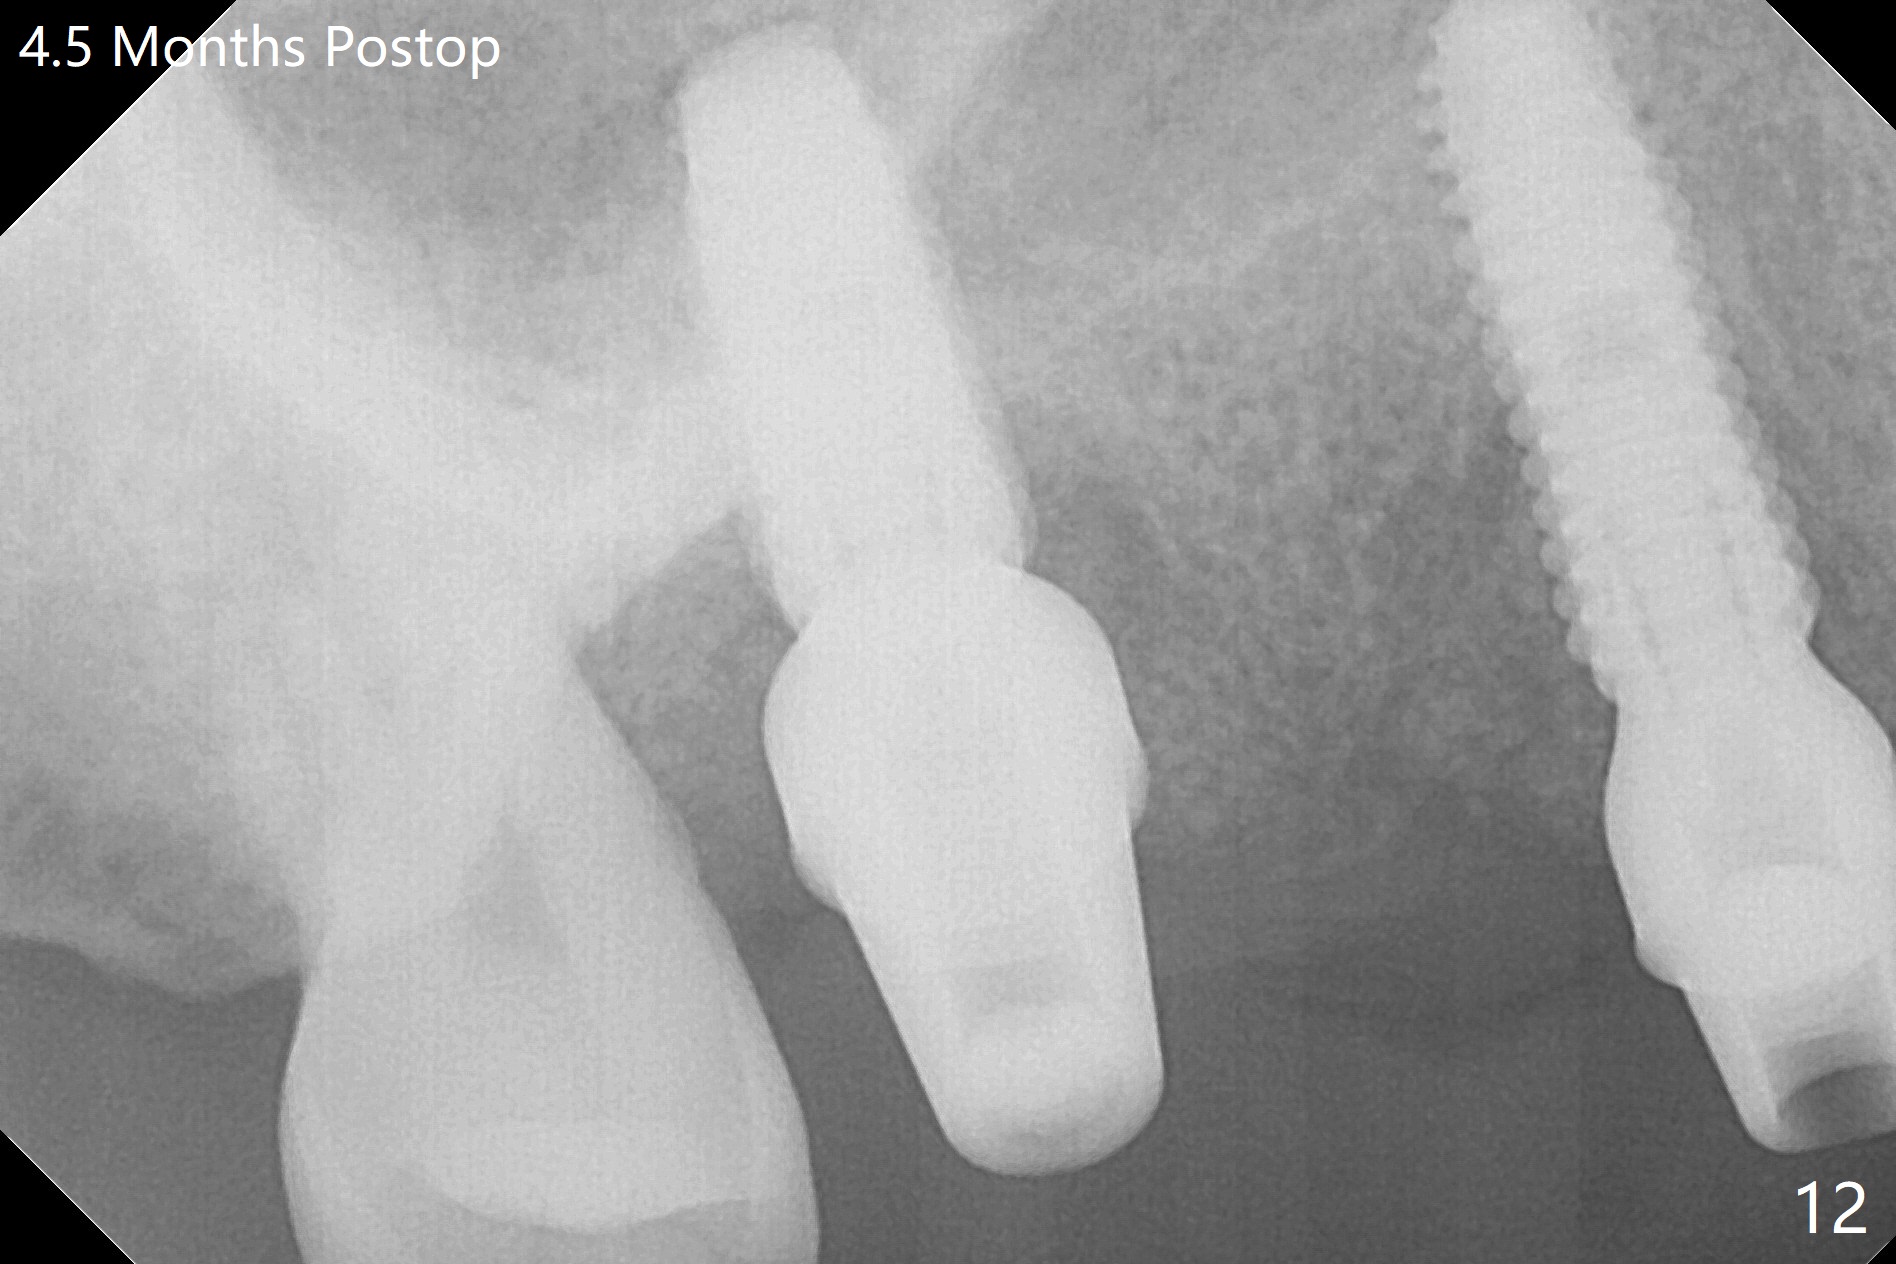

The 36-year-old man (ex-smoker, quit for 4-5 years) insists upon #3 and 5 extraction first for implants, in spite of more severe infection at #7, 14,19,30 (Fig.1-4). The gingiva around #23-26 implants is healthy 3 weeks postop (Fig.5). The initial depths at #3 and 5 are 8.5 mm (bone-level) and 18 mmm (gingiva-level (13 mm (implant length) + 5 mm cuff), respectively. When a drill penetrates the sinus floor, confirm the depth. After use of 3.8 mm drill, 4.5 mm tap drill is inserted at #3 without stability, while a 4.5x13 mm implant is placed at #5 with primary stability (Fig.6,7). Then a 5x11.5 mm is placed at #3 subcrestal proximally after sinus lift with Vanilla graft (without sinus membrane perforation; Fig.8). The implant at #5 is seated ~1 mm deeper (subcrestal mesially (^^); supracrestal distally (^)); allograft is placed around the implants prior to insertion of 6.5x7(5) and 5.5x4(5) mm abutments; last more allograft is added (Fig.9 *, 10). The implants seem to have been osteointegrated 4.5 months postop (Fig.11,12). The gingiva is healthy around the implants without bone loss 3 months post cementation (Fig.13,14).